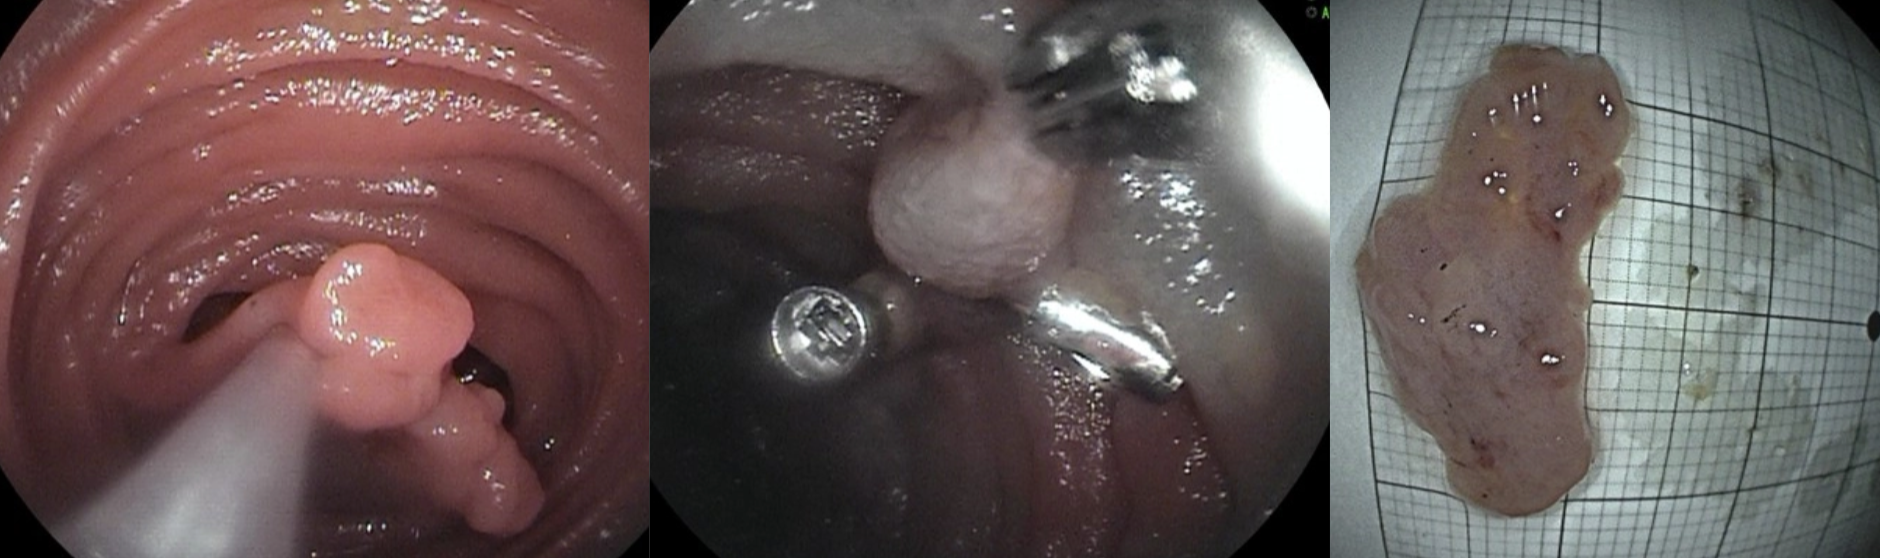

一次完整内镜下切除小肠长蒂息肉